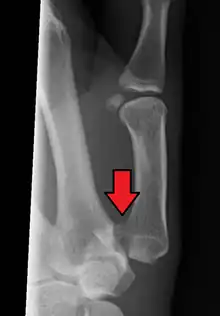

Bennett fracture

Bennett fracture on x-ray

Bennett fracture is a type of partial broken finger involving the base of the thumb, and extends into the carpometacarpal (CMC) joint.[1]

This intra-articular fracture is the most common type of fracture of the thumb, and is nearly always accompanied by some degree of subluxation or frank dislocation of the carpometacarpal joint.